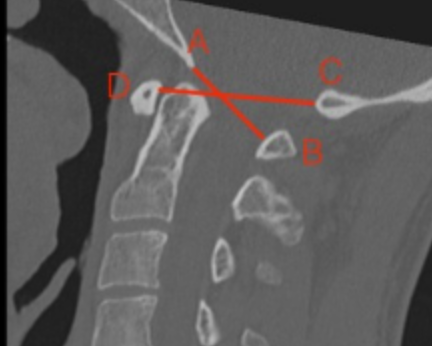

Image Type Cervical Spine X-Ray CT Scan MRI Scan Atlantodental Interval (ADI) Basion–Axial Interval (BAI) Basion–Dens Interval (BDI) Canal Occupying Ratio (COR) Clivo-Axial Angle Facet Joint Overlap (Percent Overlap Method) Facet Joint Step-Off/Dislocation Grabb-Oakes Measurement (pB - C2 line) Occipital Condyle–C1 Interval (CCI) Posterior Atlantodental Interval (PADI) Power’s Ratio Sagittal Vertical Axis (SVA) Segmental Angle Translation on Sagittal Reconstruction